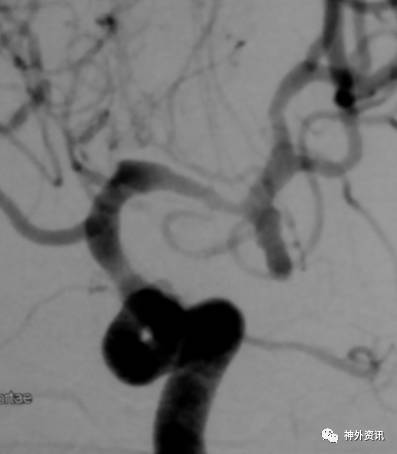

大C塑形

10mm以上的大动脉瘤:

(1)C型头端完全进入动脉瘤囊内,微导管的盘旋有利于均匀填塞

(2)避免微导管头端过早踢出

病例一